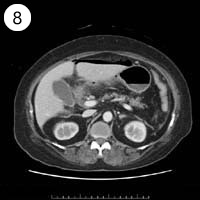

57歳 女性

単純CT

造影CT